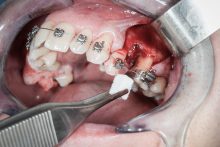

• Użycie drobin kości własnej do pokrycia ubytków na niewielkim obszarze, jak obnażenia gwintu implantu podczas implantacji, obnażenie korzeni zęba czy furkacji korzeniowych. Wiórki kostne pobierane są podczas zabiegu specjalnymi aplikatorami (skrobaczkami) z powierzchni kości szczęk i żuchwy.

Zabieg odbudowy zębodołu powinno się wykonać możliwe jak najszybciej po usunięciu zęba. Jego celem jest odbudowa naturalnej objętości kości w miejscu utraconego zęba, a następnie szybkie wprowadzenie implantu. Najlepsze rezultaty uzyskuje się przy zastosowaniu biomateriału w formie bloczków kolagenowych lub granulatu, które dają trwałe efekty odbudowy oraz optymalną funkcję i estetykę odtworzonych koron zębów na wszczepionym implancie.

Procedury te są stosowane w sytuacji niedostatecznej ilości kości, skutkującej odsłonięciem gwintu, podczas gdy wszczepiamy implanty stomatologiczne lub też jako zabiegi poprzedzające ich wprowadzenie.​